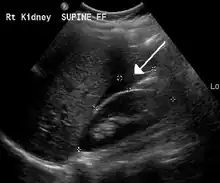

The use of ultrasound has become the standard of care when preparing a patient for paracentesis. Confirmation of an ascitic effusion reduces the risks associated with a dry or blind tap of the abdomen. Anatomic landmarks, such as the midline linea alba approach, were traditionally used as reference points for needle insertion. Phased array or curvilinear ultrasound transducers are typically used in the hospital and outpatient setting to identify ascites in the abdominal cavity. Fluid within the abdominal cavity appears hypoechoic or anechoic (black) on ultrasound. Morison's pouch (hepatorenal recess) is a common starting location in concordance with ultrasound FAST (focused assessment with sonography for trauma) exam. Fluid collection can occur in a number of different locations and may be difficult to find, especially if the patient only exhibits a small volume of ascites. Measurement of the amount of fluid within the abdominal cavity is not necessary or very successful. Identification of sufficient fluid within the abdominal cavity for fluid analysis or to achieve a therapeutic benefit is all that is required to proceed to paracentesis. Ultrasound guidance of the paracentesis can also be used as an additional safety measure to ensure the needle stays within the ascitic fluid and avoidance of important vessels within the abdominal cavity. [5]